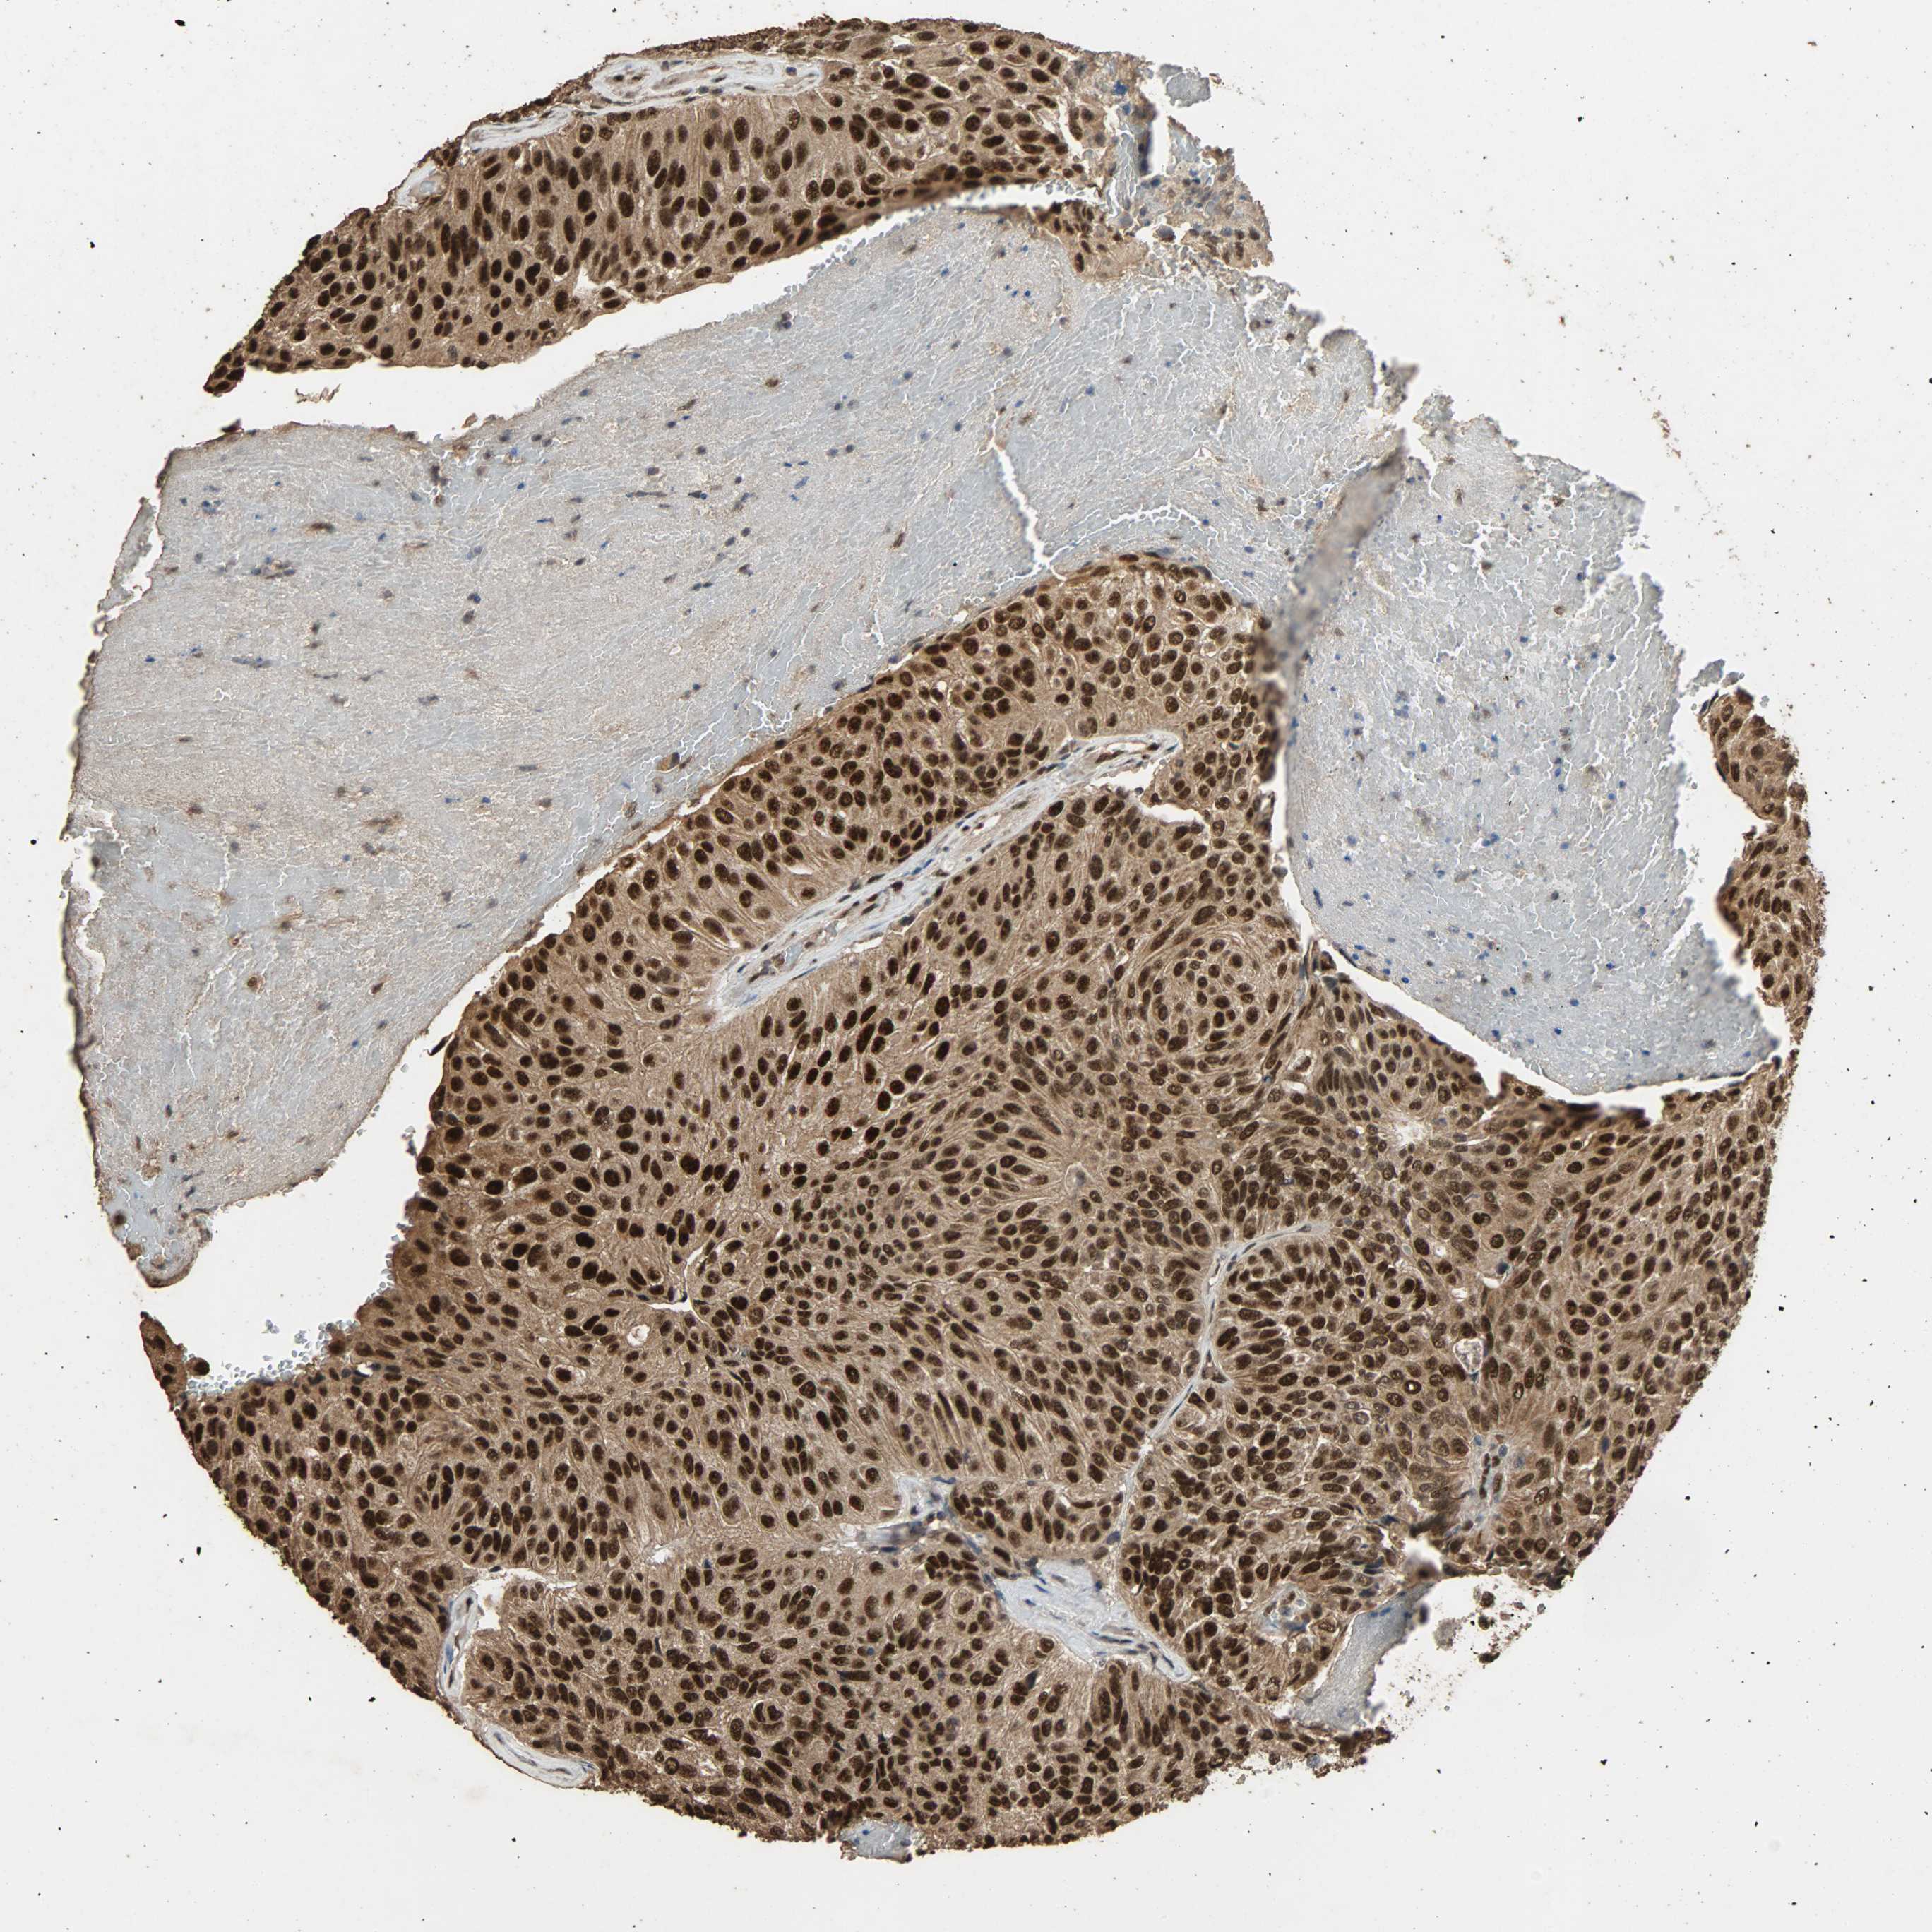

UROTHELIAL CANCER - Protein expressioni

A mouse-over function shows sample information and annotation data. Click on an image to view it in a full screen mode. Samples can be filtered based on level of antibody staining by selecting one or several of the following categories: high, medium, low and not detected. The assay and annotation is described here.

Note that samples used for immunohistochemistry by the Human Protein Atlas do not correspond to samples in the TCGA dataset.

Antibody stainingi

Antibody staining in the annotated cell types in the current human tissue is reported as not detected, low, medium, or high, based on conventional immunohistochemistry profiling in selected tissues. This score is based on the combination of the staining intensity and fraction of stained cells.

Each image is clickable and will lead to virtual microscopy that enables deeper exploration of all samples and also displays staining intensity scores, fraction scores and subcellular localization as well as patient and tissue information for each sample.

Antibody HPA005559

Staining

High

Medium

Low

Not detected

Intensity

Strong

Moderate

Weak

Negative

Quantity

>75%

75%-25%

<25%

None

Location

Nuclear

Cytoplasmic/membranous

Cytoplasmic/membranous,nuclear

Urothelial carcinoma, High grade

Urothelial carcinoma, Low grade